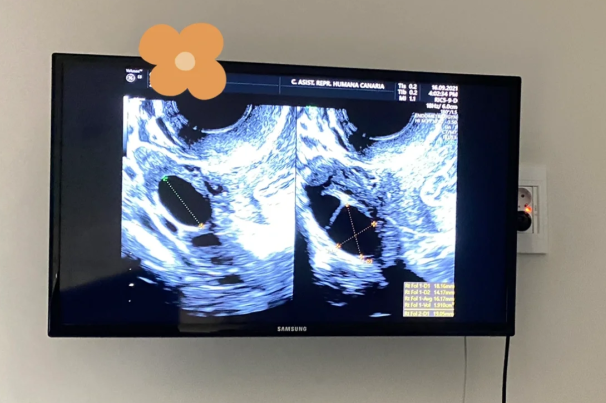

在建档并进入试管婴儿周期后,我经历了第一次促排卵。在这个阶段,我进行了为期9天的针剂治疗,总共花费了5850元。随后是夜针,费用为1050元。36小时后进行取卵手术,费用为11000元。由于第一次取卵的结果并不理想,我们进行了第二次促排卵。

第二次促排卵的第一天进行了B超检查,费用为350元。接下来的10天是促排卵,总共花费了5850元。第二次促排卵结束后,依然进行夜针治疗,费用为750元,而36-38小时后的卵子取得费用为13000元。